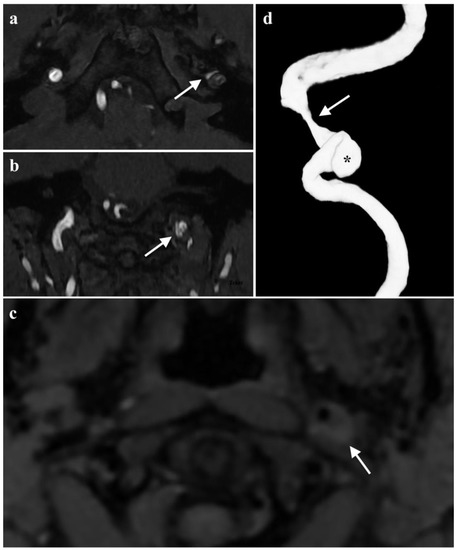

2.2. Diagnosis